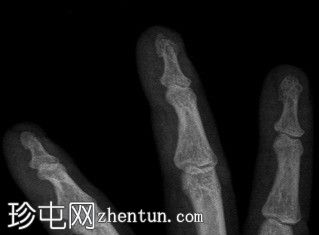

患者一天前因40公斤重的沙井事故,右手食指和中指遭受挤压伤。

X光片

斜位

右手X光片显示中指远端指骨末端失去正常的光滑轮廓,皮质轮廓不规则,提示远端骨折畸形。骨折在斜位片上更容易被看到,并伴有轻度移位和周围软组织肿胀。

X光片结果显示中指远端指骨末端骨折,皮质轮廓不规则,正常轮廓丧失,可能由直接创伤引起,例如重物撞击或挤压伤。